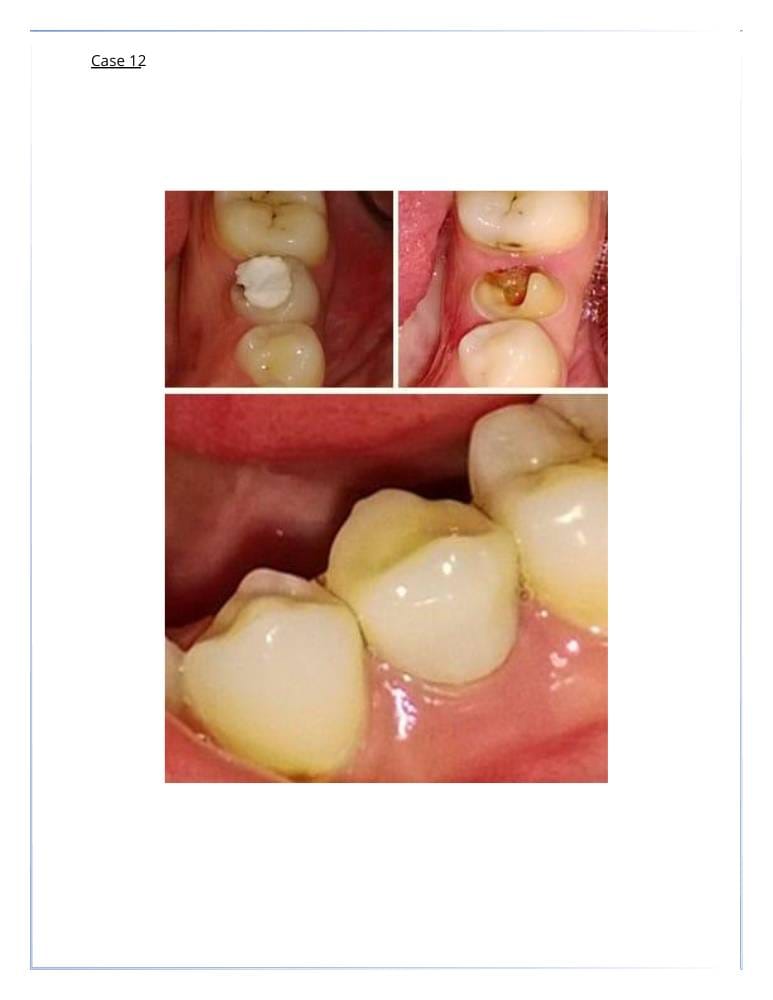

- علاج التسوس : من خلال الحشوات التجميلية.

- علاج الأسنان : المكسورة أو المتضررة.

تركيبات الأسنان

- التيجان والجسور الثابتة.